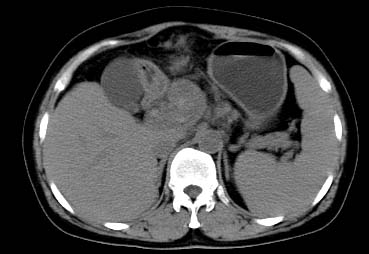

以下是引用西北一只狼在2008-6-30 20:58:00的发言:[br]肝左叶胆管细胞ca并肝门淋巴结转移、胰腺、胃小弯浸润

以下是引用ydx_74在2008-6-30 21:54:00的发言:[br]左叶胆管细胞ca并肝门淋巴结转移、胰腺、胃小弯浸润